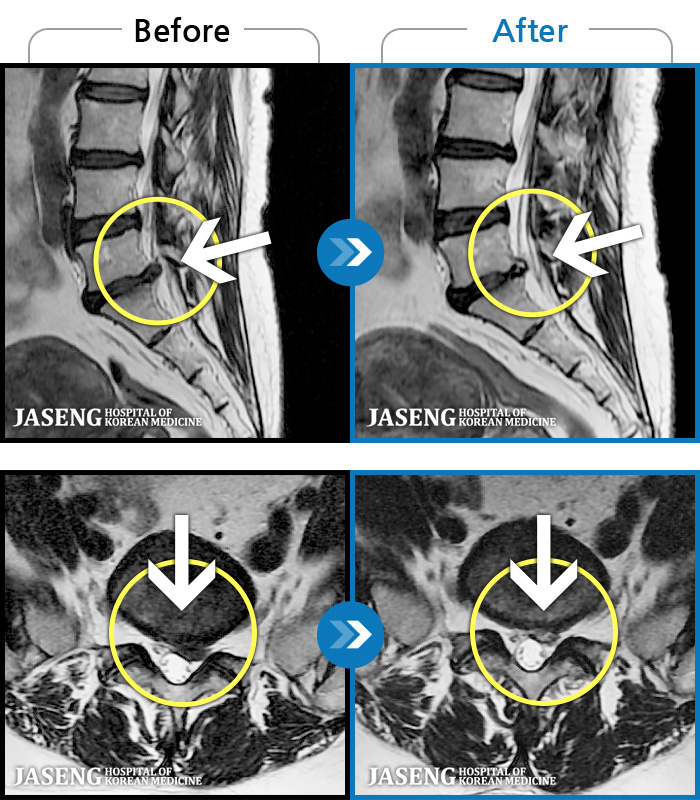

MRI ġ

1,245 MRI ũ ʸ Ȯϼ.